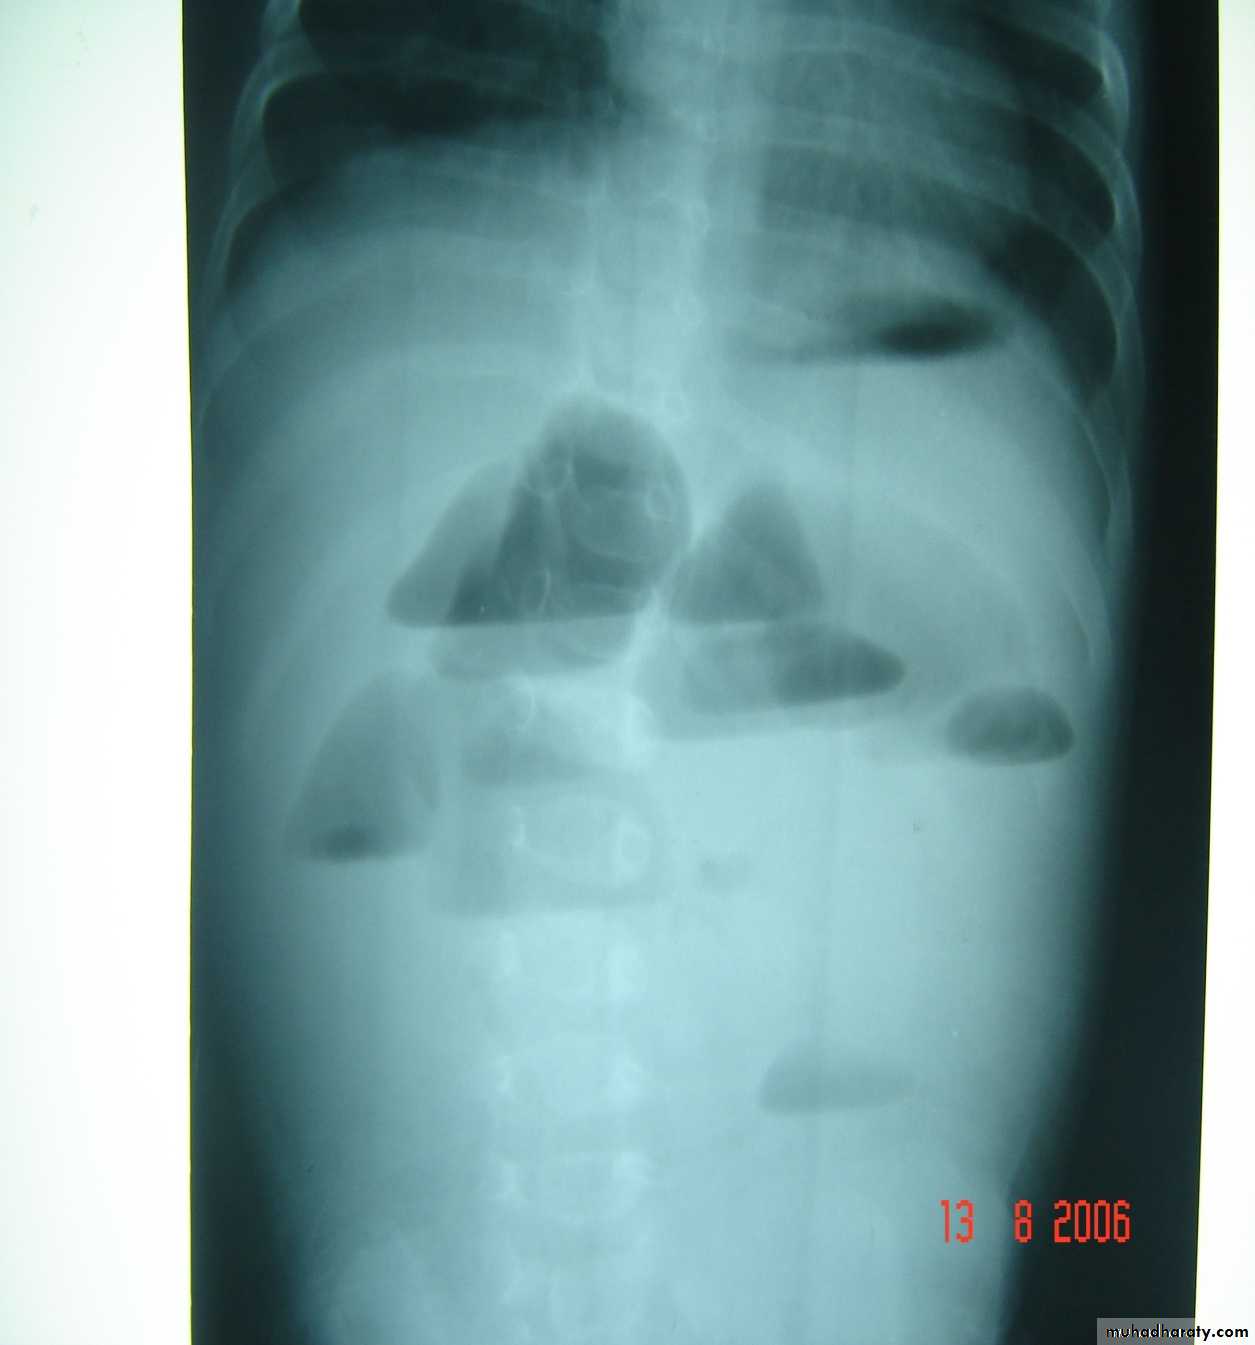

Meconium ileus